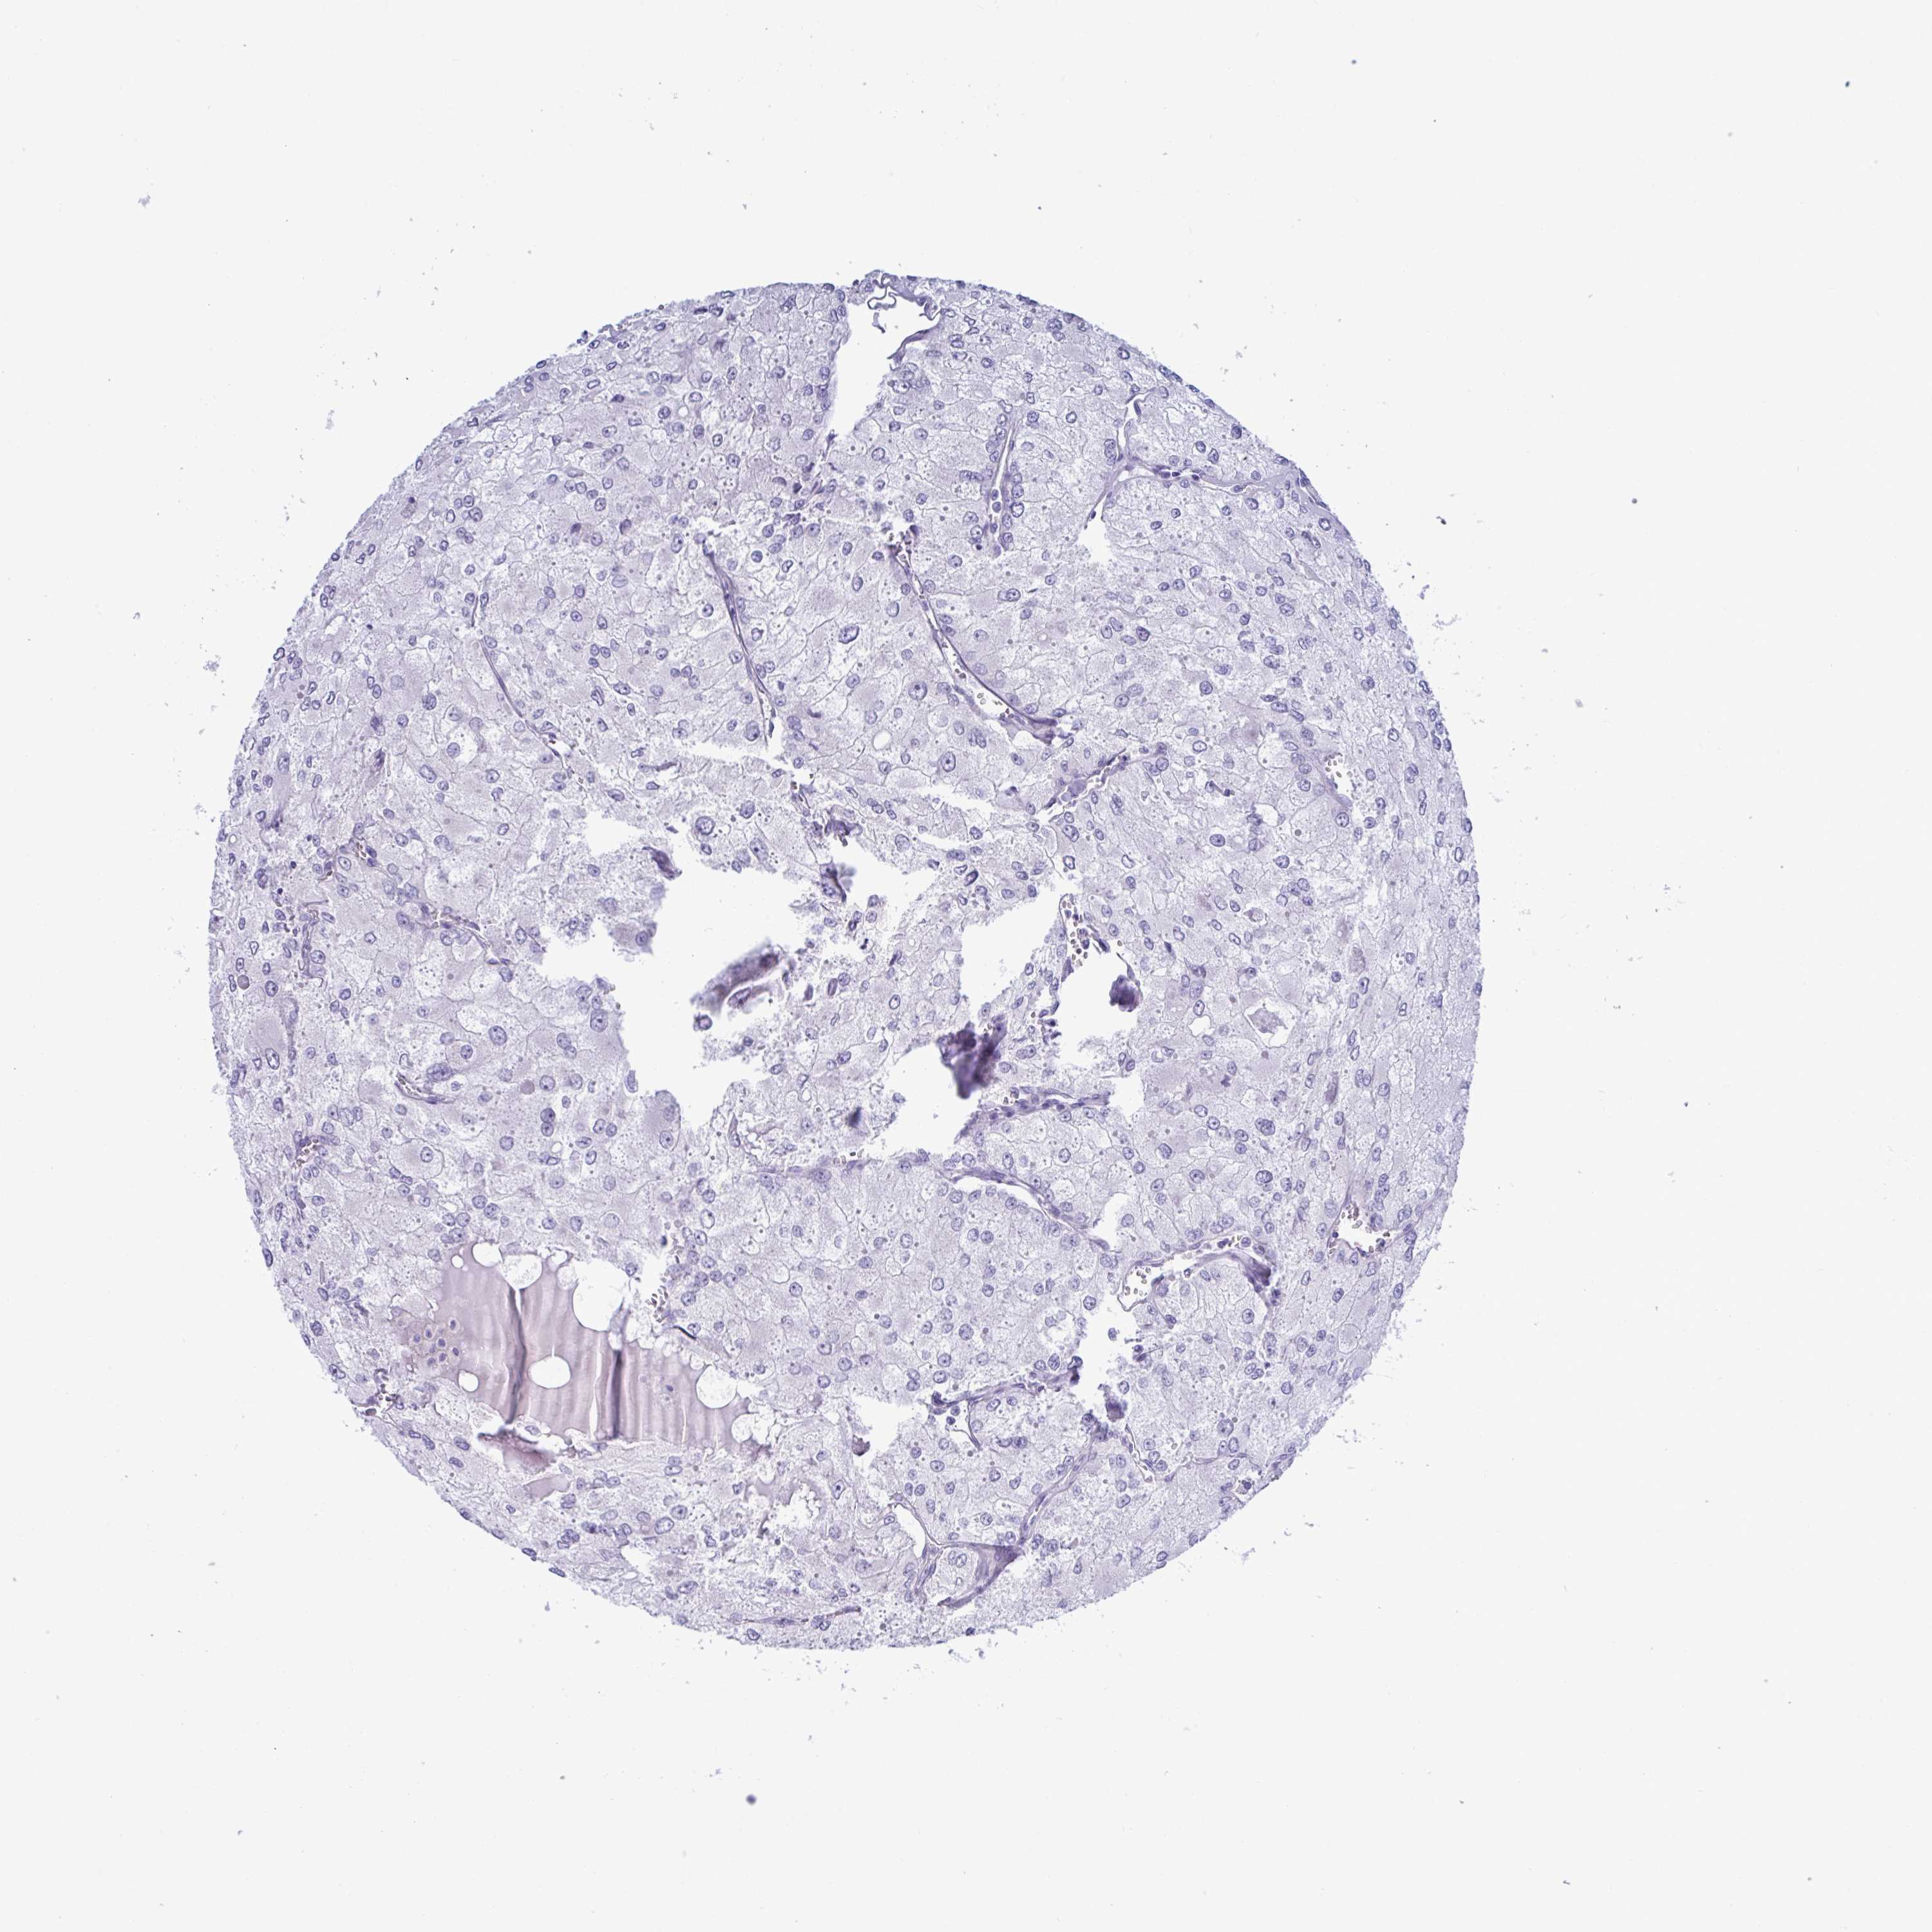

KIDNEY RENAL CLEAR CELL CARCINOMA (TCGA) - Interactive survival scatter ploti

The Survival Scatter plot shows the clinical status (i.e. dead or alive) for all individuals in the patient cohort, based on the same data that underlies the corresponding Kaplan-Meier plots. Patients that are alive at last time for follow-up are shown in blue and patients who have died during the study are shown in red.

The x-axis shows the expression levels (FPKM) of the investigated gene in the tumor tissue at the time of diagnosis. The y-axis shows the follow-up time after diagnosis (years). Both axes are complimented with kernel density curves demonstrating the data density over the axes. The top density plot shows the expression levels (FPKM) distribution among dead (red) and alive patients (blue). The right density plot shows the data density of the survived years of dead patients with high and low expression levels respectively, stratified using the cutoff indicated by the vertical dashed line through the Survival Scatter plot. This cutoff is automatically defined based on the FPKM cutoff that minimizes the p-score. The cutoff can be changed by dragging the vertical line or by entering a cutoff value in the square labeled "Current cut-off".

Under the Survival Scatter plot the p-score landscape (black curve; left axis) is shown together with dead median separation (red curve; right axis). Dead median separation is the difference in median mRNA expression between patients who have died with high and low expression, respectively. It is calculated as follows: median FPKM expression of dead patients with high expression - median FPKM expression of dead patients with low expression. This is intended to aid the user in visually exploring custom cutoffs and the associated p-scores and dead median separation.

Individual patient data is displayed and can be filtered by clicking on one or more of the category buttons on the top of the page. Categories describing expression level and patient information include: high, low, alive, dead, female, male and tumor stages. The scale of the x-axis can be toggled between linear and log-scale by clicking on the "x log" button. Mouse-over function shows TCGA ID, patient information and mRNA expression (FPKM) for each patient.

& Survival analysisi

Kaplan-Meier plots summarize results from analysis of correlation between mRNA expression level and patient survival. Patients were divided based on level of expression into one of the two groups "low" (under cut off) or "high" (over cut off). X-axis shows time for survival (years) and y-axis shows the probability of survival, where 1.0 corresponds to 100 percent.

MED11 is not prognostic in Kidney Renal Clear Cell Carcinoma (TCGA)